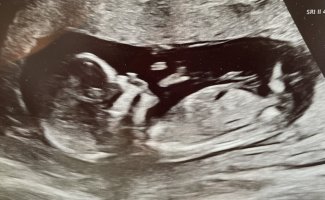

Gutt?!

Spennende altså. Tror vi må få vite kjønn på ordinær UL for jeg klarer antageligvis ikke å vente, haha.Gutt?!

Men så ble jeg litt usikker med en gang jeg postet. Kanskje den er mer rett? Isåfall jente!Spennende altså. Tror vi må få vite kjønn på ordinær UL for jeg klarer antageligvis ikke å vente, haha.

Dette må da være en gutt?Noen som vil tolke denne? 15+4. Vis vedlegget 459049

Ja, jeg synes kanskje den er mer rett. Har sittet og studert videoklippet flere ganger nå og tenker den er mer i linje med ryggraden enn oppover. Kjempespennende uansett!Men så ble jeg litt usikker med en gang jeg postet. Kanskje den er mer rett? Isåfall jente!